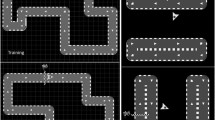

Motor Sequence Learning Task

Motor sequence performance was assessed by an adapted version of the sequential finger tapping task introduced by Karni and colleagues [4], which has also been employed extensively in our laboratory [29,30,31]. In each of both experimental sessions, participants were asked to practice one of two different, equally difficult five-element finger-tapping sequences on a four-button customized keyboard. Sequence 1 was “4-1-3-2-4” and sequence 2 was “1-4-2-3-1” (1 = index finger, 2 = middle finger, 3 = ring finger, 4 = little finger). The order of type of sequence allocation to session 1 or session 2 was balanced across all participants. To verify that participants had explicit knowledge of the finger-tapping sequence prior to training onset, they were required to slowly repeat the sequence until they reproduced it three times in a row without mistakes. The training part encompassed 14 successive blocks of sequence execution which were separated by 25-s rest periods. Participants were instructed to perform the sequence as fast as possible while making as few errors as possible. Unbeknownst to the participants, each task block was terminated after 60 key presses to make sure that all participants performed the same number of training movements (i.e., all participants received the same amount of training). Therefore, a maximum of 12 correct sequences could be executed within each block of training. The beginning of a training block was indicated by a green fixation cross in the middle of a computer screen in front of the participants, which turned red (i.e., after 60 button presses on the keyboard) to indicate the beginning of a 25-s rest block. The delayed retest session after an interval of 8 h encompassed only 4 blocks of the task. During training and retesting no information on the sequence was presented to the participants (Fig. 1).

Experimental design. a Finger positioning on the keyboard and sequence order exemplary for the right hand. b The experiment consisted of two sessions which were separated by at least 14 days. Each session contained a training phase and a delayed retest phase. Training (11 am) encompassed 14 task blocks of 60 key presses and 25-s rest periods in-between blocks. Delayed retesting took place 8 h later (7 pm) and encompassed 4 blocks of the task